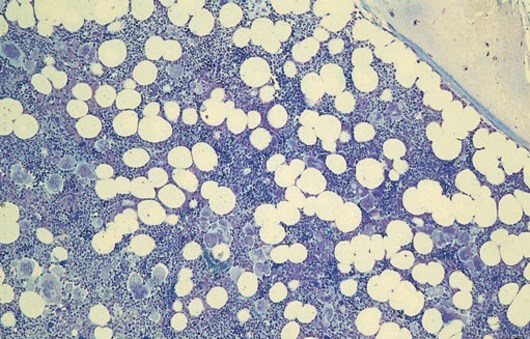

Außer dem Nachweis einer Mutation ist die Knochenmarkpunktion (KMP) die wichtigste Methode, um eine ET eindeutig diagnostizieren zu können – und daher meist unumgänglich. Die veränderten blutbildenden Zellen und die Architektur des Knochenmarks lassen sich nur mittels Knochenmarkzytologie und -histologie unter dem Mikroskop exakt untersuchen und nur so der MPN-Subtyp genau einordnen.

Typischer KMP-Befund bei einer ET

Die Ergebnisse der Knochenmarkuntersuchung stellen die einzige Möglichkeit dar, die einzelnen MPN sicher voneinander zu unterscheiden und sind deshalb für die weitere Behandlung und Prognose von großer Wichtigkeit. Daher empfiehlt es sich, die Gewebeprobe ggf. zusätzlich von einem spezialisierten Referenzlabor hämatopathologisch zweitbegutachten zu lassen.

Letztlich stellt jede Knochenmarkpunktion nur eine Momentaufnahme dar, die in der Regel keine Aussage über den weiteren Verlauf der Erkrankung zulässt. Der Befund kann abhängig von der Entnahmestelle variieren.

https://onlinelibrary.wiley.com/doi/10.1002/ajh.25270 - Mikroskopie-Abbildung – mit freundlicher Genehmigung aus: Torsten Haferlach, Hämatologische Erkrankungen, Atlas und diagnostisches Handbuch, Springer-Verlag Berlin Heidelberg 2020, ISBN 978-3-662-59546-6